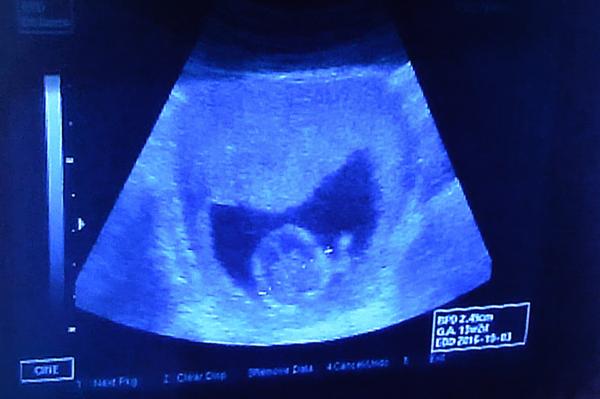

Dnes jsem byla po 4 týdnech na kontrole. Hlavička měřila 2,41cm (13+0) a tělíčko při prvním měření 6,13cm (13+0) a když měřil znova aby vytiskl fotečku tak jen 5,95cm (12+6) . Není to málo ? Všude se píše,že by měl mít tak 8cm

Přikládám foto z ultrazvuku před 4 týdny + dnešní + fota focené dnes mobilem z monitoru.